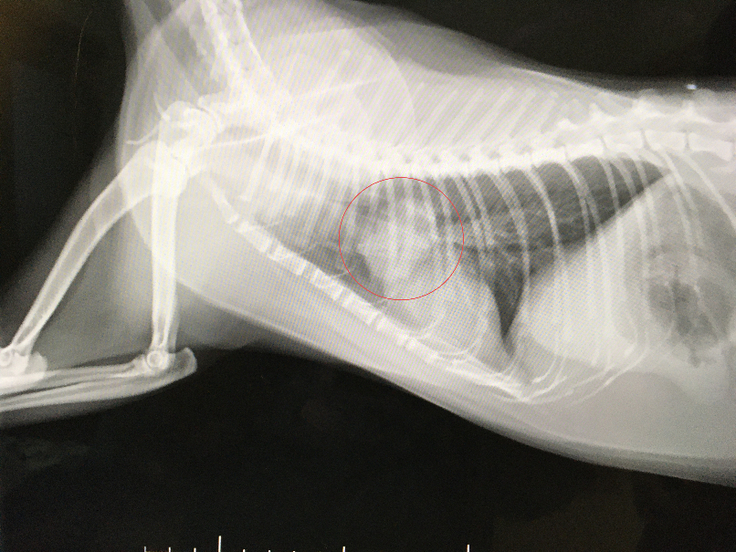

レントゲンで見つかった肺腺瘤(肺腺癌の疑い)や大動脈血栓塞栓症の状態確認へCTの撮れる、日本で技術のある腫瘍の専門医の先生を紹介していただき、先日訪問し検査をしました。

10月1日 肺腺瘤(肺腺癌の疑い)と確認。ほぼ肺腺癌で間違いないので転移してないから早急に取ったほうがいい。と言われました。

画像は、3.2cmの肺腺瘤(肺腺癌疑い)です。猫の肺腺瘤(肺腺癌疑い)は症例が少なく、開胸手術等や高度になるため、費用がとても高額になります。

10月15日(日)13:00~16:00 肺腺瘤(肺腺癌の疑い)を摘出手術を行いました。

手術後、右肺の中葉に出来た腫瘍が綺麗にとれました。

右肺腺瘤に膿瘍もあったそうですが、綺麗に取れたとのこと。

獣医師より『肺腺瘤はギリギリ癒着もなく、綺麗に取ることが出来ました、肺腺瘤に膿瘍も付着し発見したけど、薄皮一枚で繋がっており体内で破裂してなかったのが幸いで、それも全て取れた』と仰っていただきました。

↑術後の画像、綺麗に肺腺瘤、膿瘍が摘出して頂いてます。